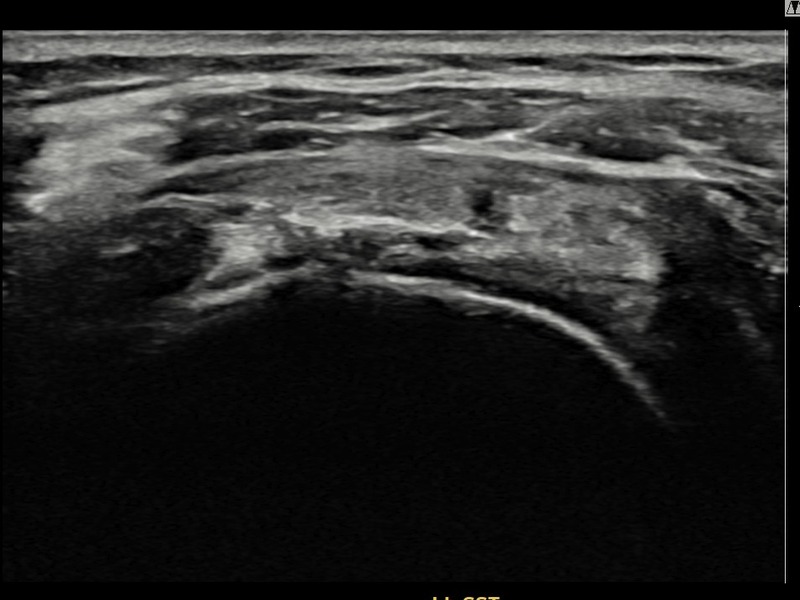

김ㅇㅇ님 · 좌측 극상근건 부착부 광범위 부분파열

좌측 어깨 극상근건 광범위 파열로 수개월간 일상생활이 어렵던 중 내원하셨습니다. 초음파 검사에서 부착부 광범위 부분파열이 확인되었으며, 어깨인대 축소봉합술 시행 후 힘줄 구조가 회복되었습니다.